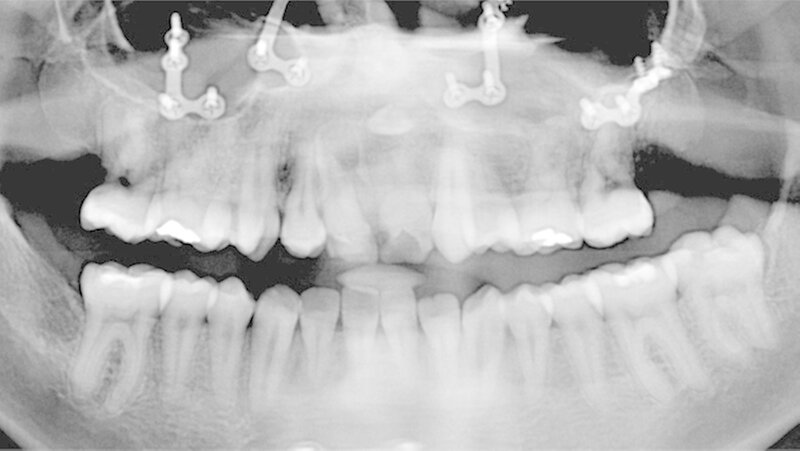

Der Patient zeigte eine operativ behandelte beidseitige Lippen-Kiefer-Gaumenspalte, sowie eine anomale Gebissformel. Zudem lagen eine Hypodontie (Agenesie der Zähne 15, 12, 22, 25) und eine Transposition zwischen Zahn 13 und 14 vor. Es wurde auch eine Schmelzanomalie mit Dysmorphie bei Zahn 11 festgestellt. Die Zähne 11 und 21 wiesen kariöse Läsionen auf. Der Patient wünschte eine ästhetische Versorgung.